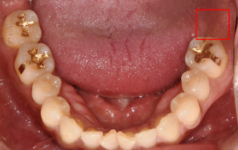

Before (전)

내원하신 분은 이미 치아를 발치까지 되어있는 상태였습니다. 치아 발치 후 상당 기간을 방치했기 때문에, 뼈이식을 진행해야 하지 않을까 걱정을 하시며 방문하셨는데요.

Before(전) : After(후)